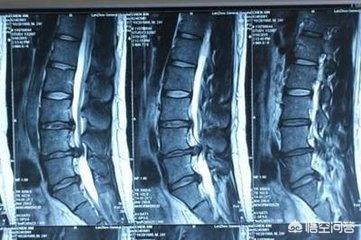

4.画像診断では、腰部筋緊張超音波検査で腰部筋の肥厚や萎縮を見ることができる。腰椎椎間板ヘルニアは、腰椎CTや腰椎MRIで診断を確定することができる。

腰椎の歪み:画像診断は一般的に正常。

腰椎椎間板ヘルニア:腰椎の正面と側面のフィルムで、腰椎の脊柱側弯、それに対応する椎間腔の狭窄、左右の不均等な幅、骨圧迫の形成などをよく見ることができる。CTとMRIは腰椎の変性の程度を正確に見ることができ、腰椎椎間板ヘルニアがあるかどうかをはっきりさせることができる。

検査と評価から

ぎっくり腰一般的な画像診断では明らかな異常所見はなく、痛みを伴うという点でのみ見ることができる。腰の痛みはより広範囲で、再発性、軽度から重度まであり、背筋のこわばりを伴う。。

4.画像

椎間板ヘルニアの画像変化を確認するためのCTまたはMRIと、評価検査を組み合わせる。

CTとMRIは腰椎椎間板ヘルニアを明確に診断でき、また両者の鑑別にもなる。

最後に、診断を確認する必要がある場合、病院に行って行う検査は、両者で異なる可能性がある。腰椎の筋緊張は、超音波検査で済む場合もある。腰の筋肉が肥厚し、萎縮しているのがわかる。一方、腰椎椎間板ヘルニアは、病理学的変化を検出するためにCTやMRIを必要とすることが多い!